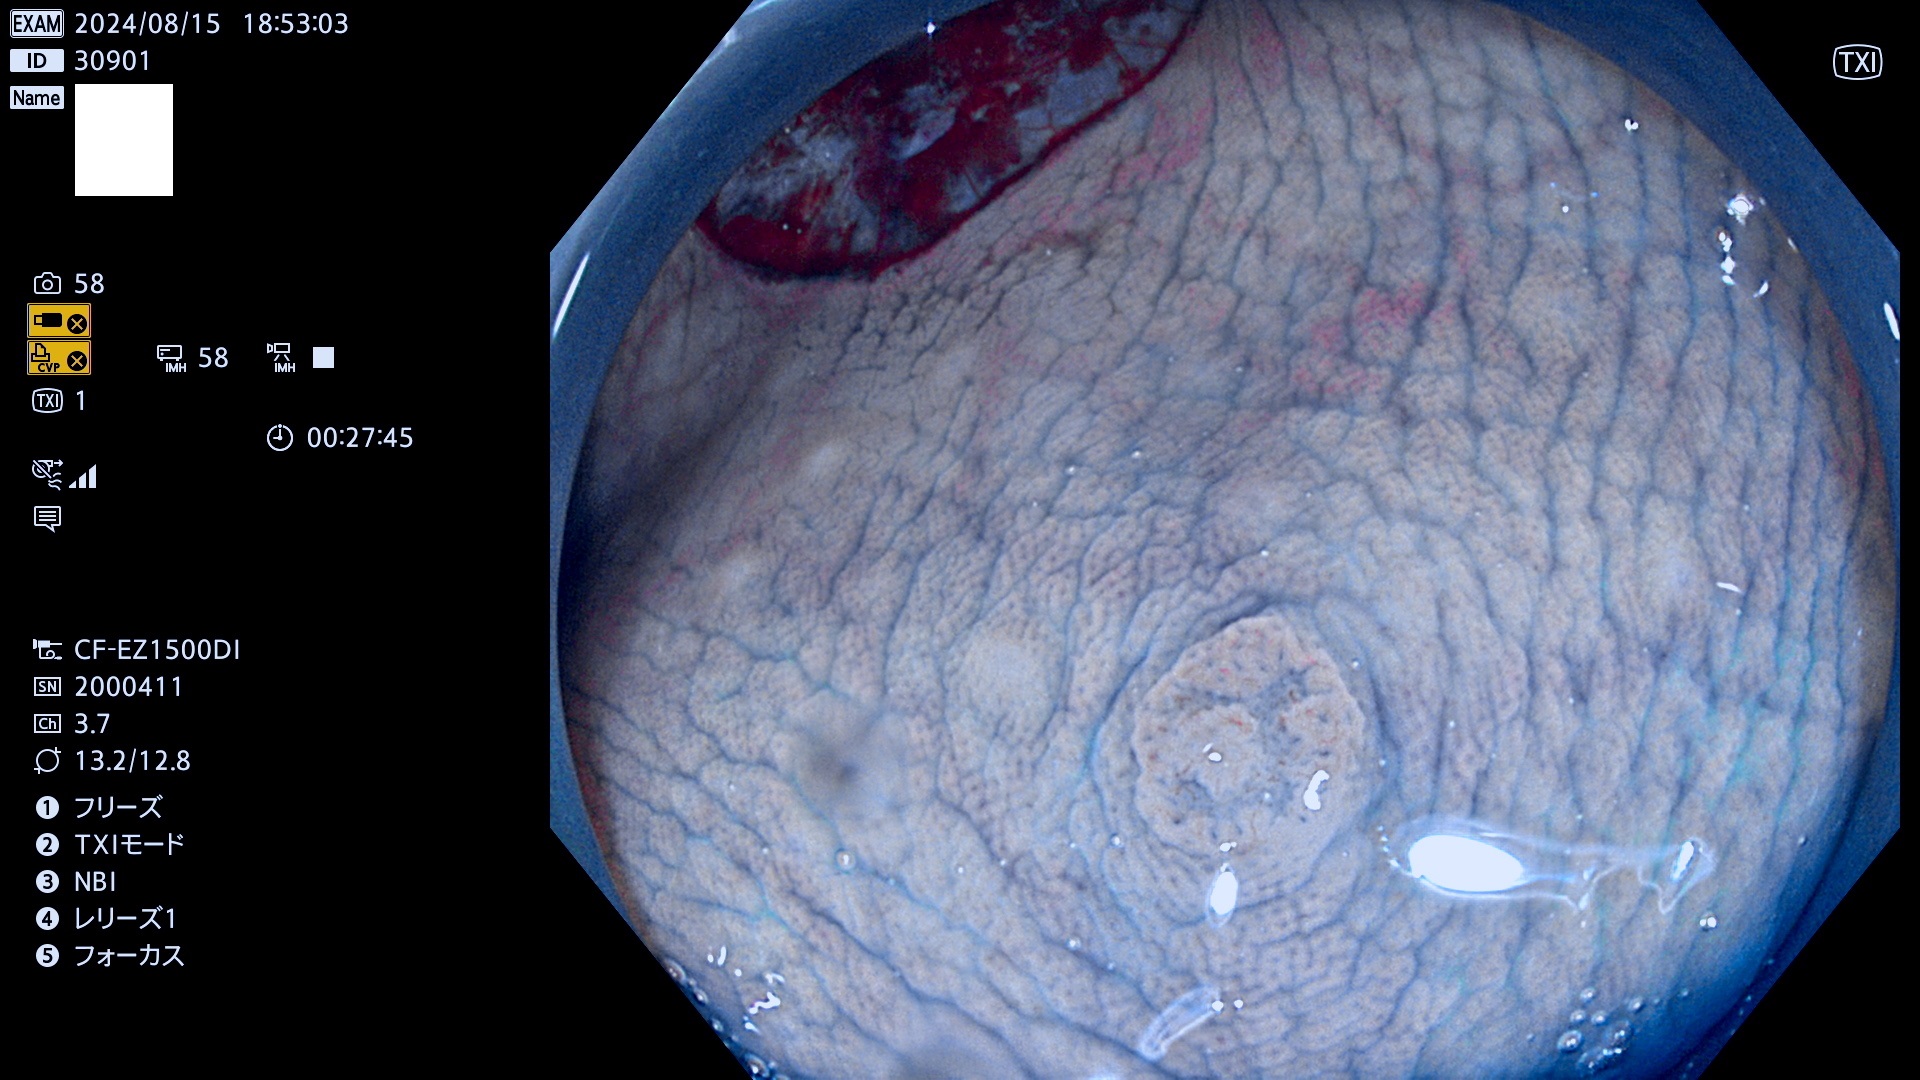

今週のUb、Uc型腺腫

完全に平坦な物をUb、陥凹している物をUcと呼びます。最も発見が難しく危険な病変です。

抽出の対象期間 2024年8月15日〜8月18の4日間(33件の検査)7件 (7/33=21%)